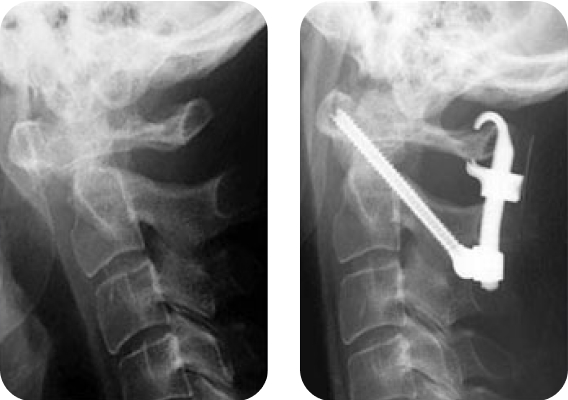

Клинический пример 1

- Пациент:

- Мужчина, 42 года

- Диагноз:

- Переломовывих С4-С5, иммобилизация в корсете Минервы.

- Лечение:

- Выполнена стабилизация системой Neon™.